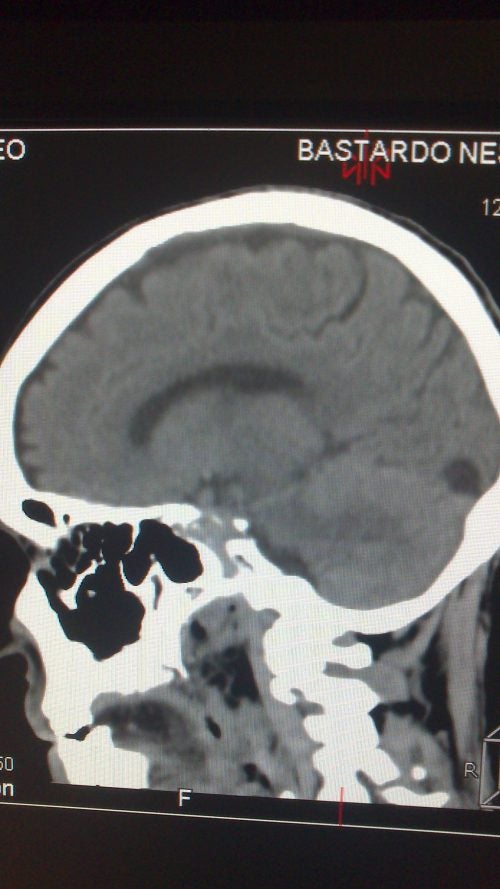

- A todos ellos les realizaron analíticas sanguíneas y tomografías cerebrales.

El resultado fue llamativo. Todos ellos afirmaron que se sentían más positivos en relación con su situación. Por su parte, las conclusiones de los análisis y las tomografías fueron muy curiosas.

- El equipo explica que se detectaron mayores conexiones cerebrales en las zonas encargadas de la gestión del estrés, de la generación de calma y de la tranquilidad.